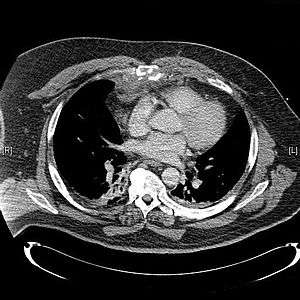

CT scan showing a comminuted sternal fracture.[1]